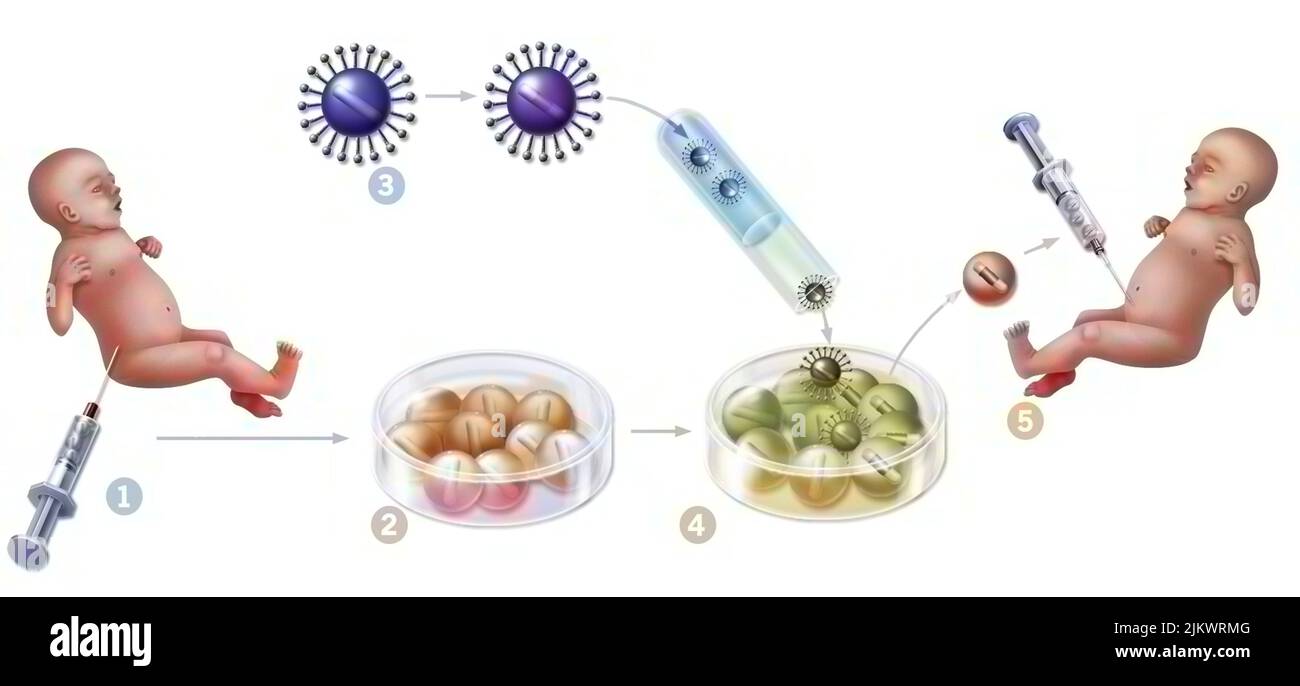

RF2JKWRMG–Thérapie génique : introduction de rétrovirus pour modifier les cellules de la moelle épinière mutées d'un nouveau-né.